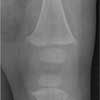

X-ray films revealed florid signs of rickets, including a rachitic rosary and cupping of ribs, and fraying and flaying of the radius, ulna, femur, tibia, and fibula (Figures 1 and 2).